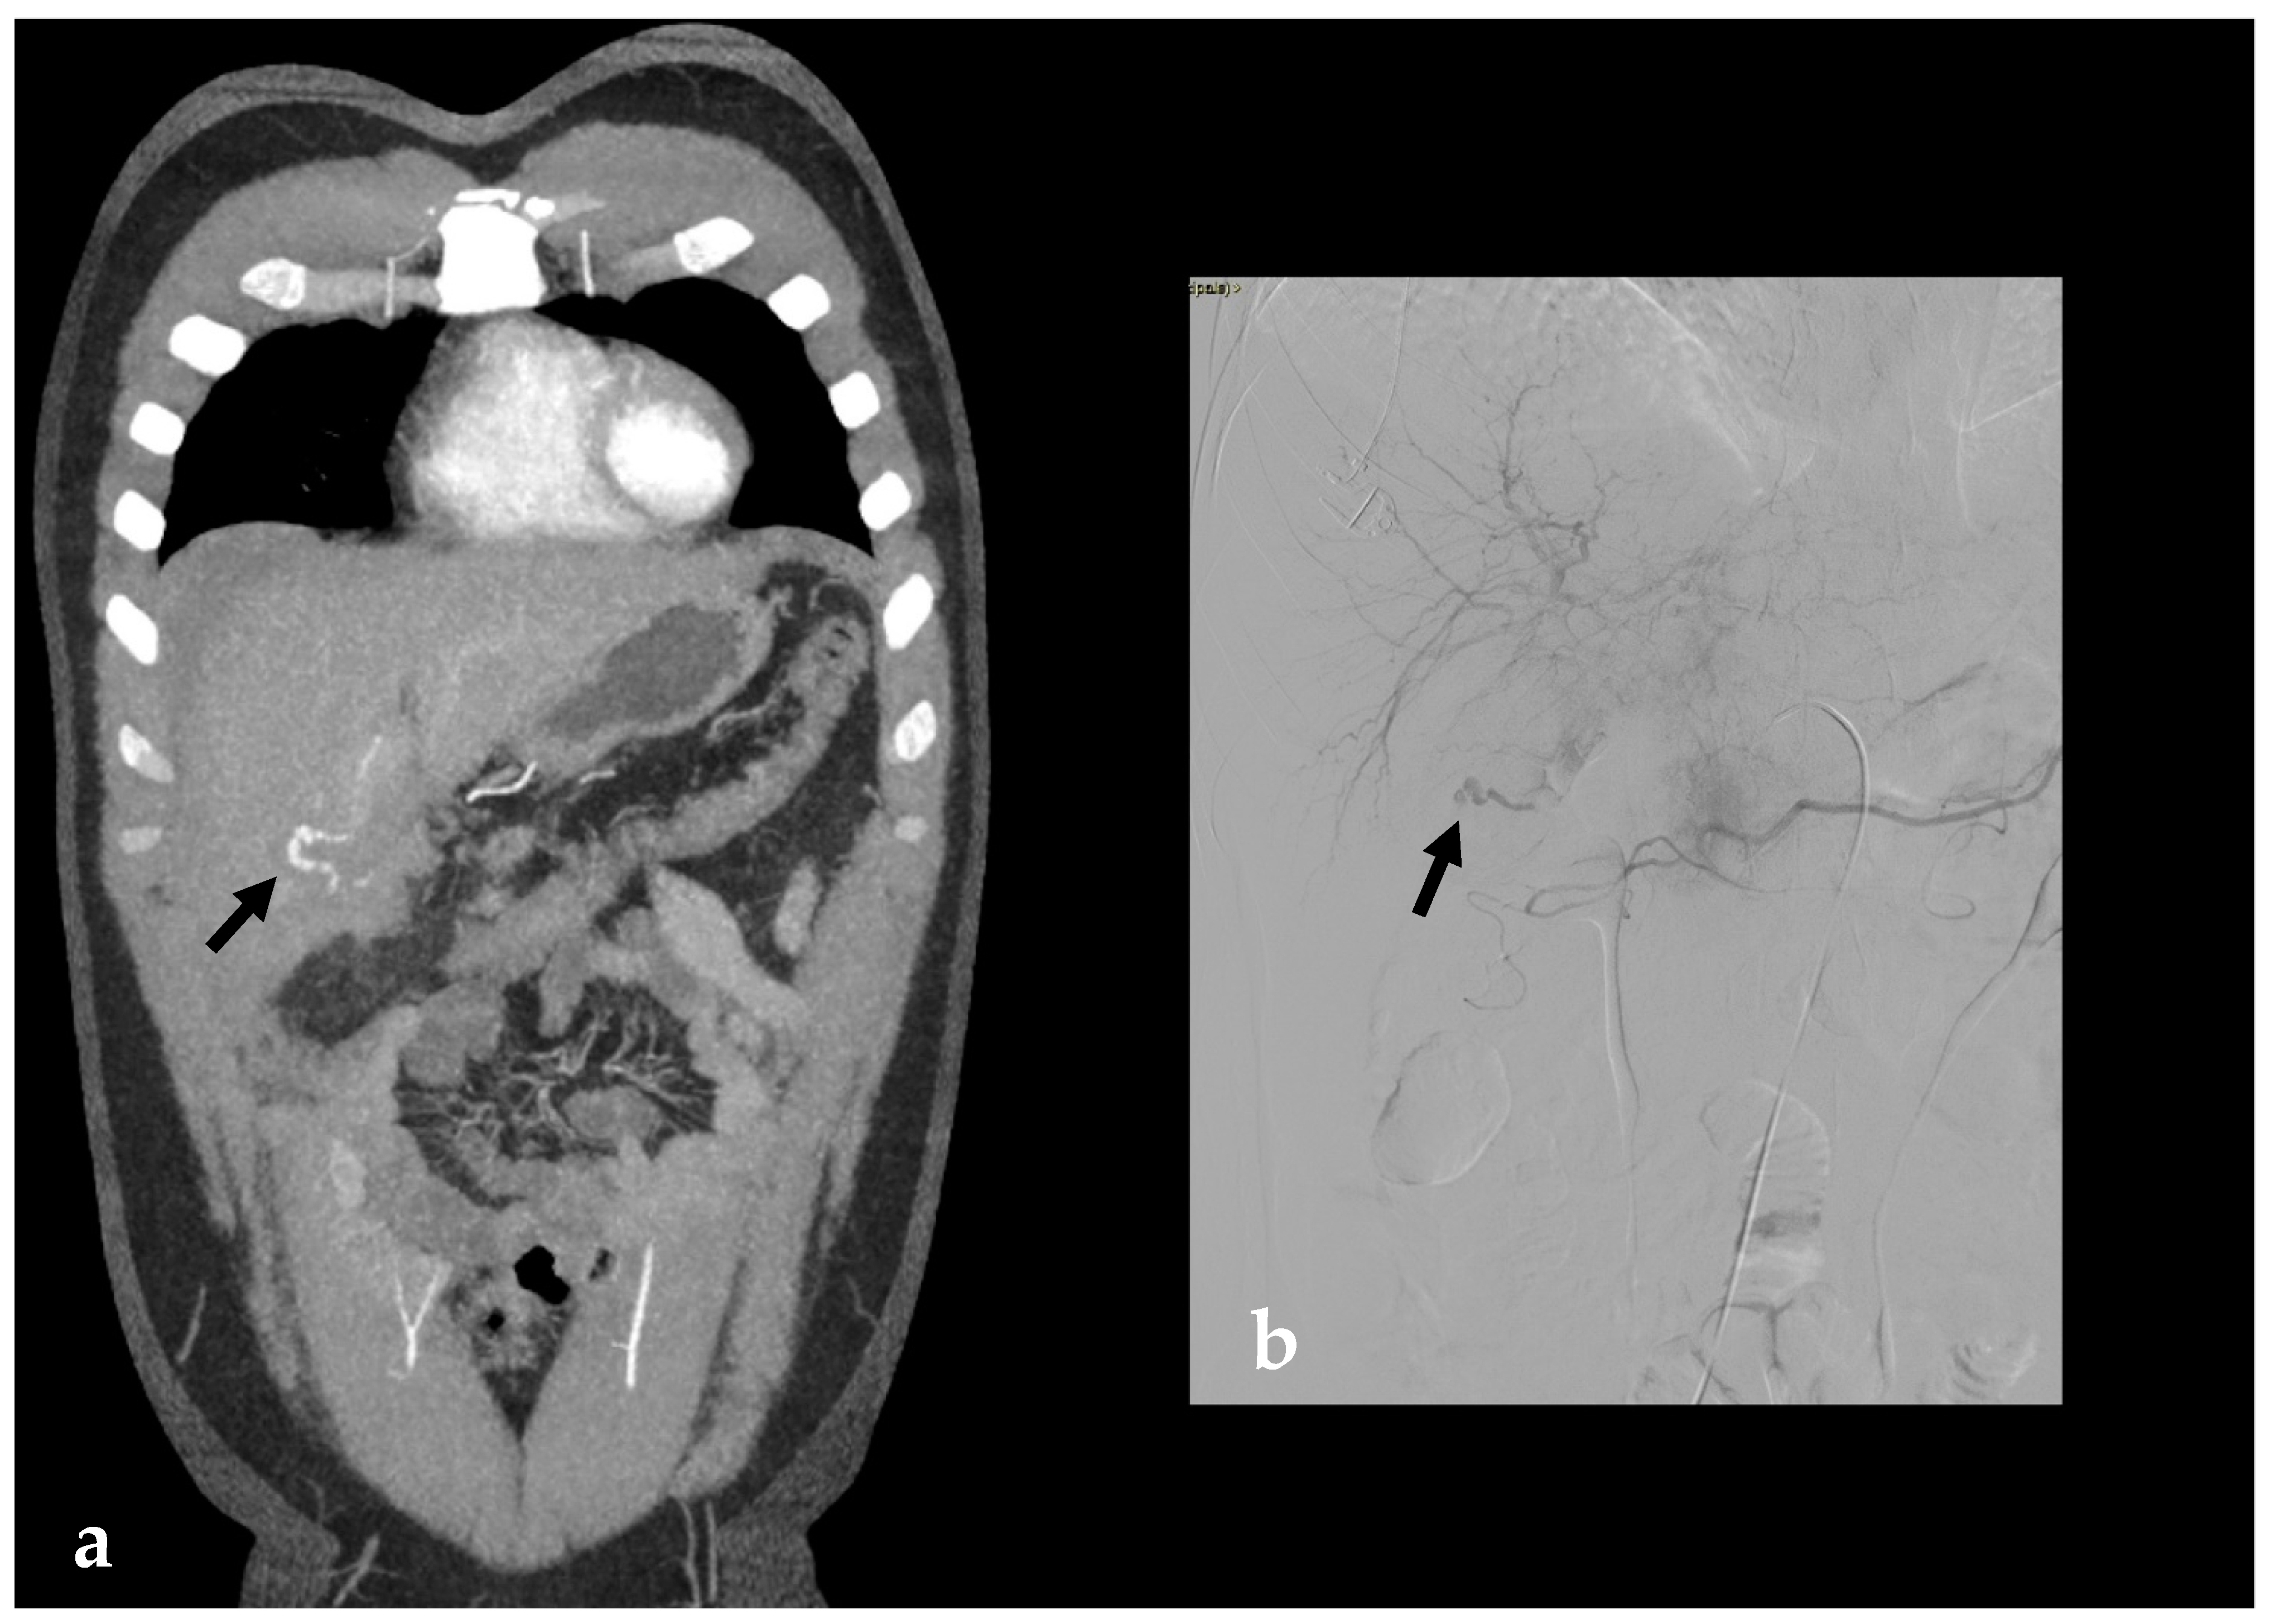

2. Imaging